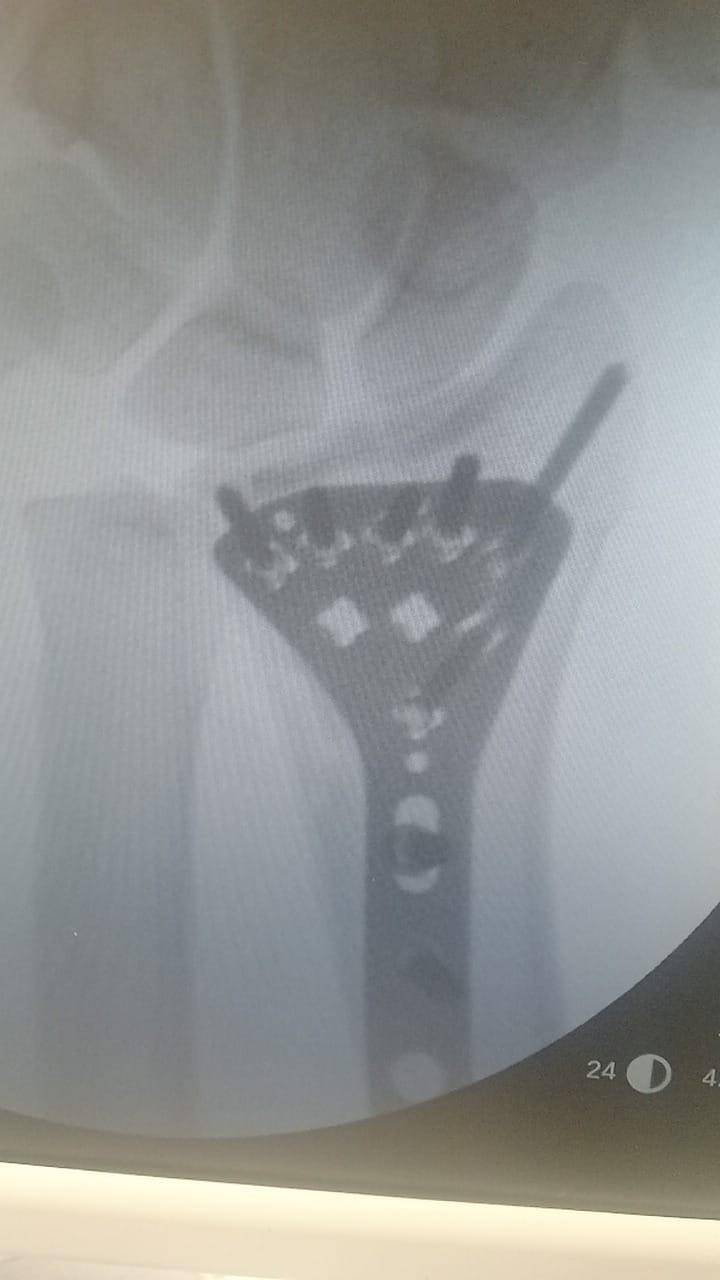

- إجراء عمليات جراحية معقدة و دقيقة في مجال العظام و المفاصل و الكسور و الإصابات ، رغم الضغط الكبير على المستشفى و أعداد المراجعين الكبيرة.

- تطبيق تقنيات جراحية حديثة و متقدمة، و ذلك في ظل التحديات التي يواجهها الفريق بسبب أعداد المرضى و المراجعين الكبيرة.